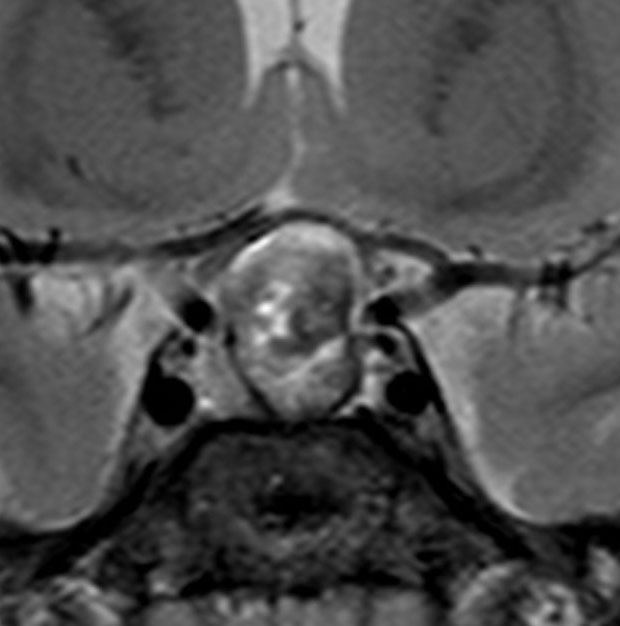

増大しても下垂体症状を出さなかった例

9歳の女の子に偶然発見された腫瘍です。何の症状もありませんでした。頭蓋咽頭腫と診断されて経過観察となりました。1年半観察しましたが腫瘍は増大して,視交差の変形が増して両耳側1/4半盲となり症候性となりました。下垂体機能は正常でした。

上のT2強調画像では,全体的に低信号で,高信号の部分が混在します。上右のCISS画像では,下垂体組織が右に変移していることが推定されます。

左がT1強調画像で高信号,右がT1ガドリニウム増強像ですが腫瘍は増強されません。正常か錐体が腫瘍の右側にくっついていて,ガドリニウム増強されています。典型的なトルコ鞍部黄色肉芽腫です。画像診断で,下垂体腺腫の腫瘍内出血とよく間違われるのですが,高信号になるのはコレステリン結晶を豊富に含むからです。ガドリニウム増強される部分がほとんどないという所見が頭蓋咽頭腫とは異なるところでしょう。

左と中央の画像でinfundibular recessの管腔が見え,左の視交差から視索の変形が強いことが解ります。右の画像では下垂体組織がトルコ鞍の右側に偏在してあります。画像では正常化錐体と明瞭な境界があるように見えるのですが,実際の手術所見では正常下垂体との境界は不鮮明でした。腫瘍のう胞からは黒褐色の内容液 machinery oil とコレステリン結晶が流出しました。厚いのう胞壁は硬膜と下垂体に強く付着して剥離するのが困難で切断して摘出しました。ラトケのう胞とはのう胞壁の厚さが異なると言えます。

術後5ヶ月のMRIです,無理して全摘出しませんでしたので残存腫瘍のように見えます。病理診断では,出血,慢性炎症性細胞浸潤を伴い,コレステリン結晶やヘモジデリンの沈着,泡沫組織球,多核巨細胞浸潤を伴った繊維性組織片に,少量の上皮組織塊があり,少量の正常下垂体組織も付着していると報告されました。施設によってはこの所見をラトケのう胞と病理診断するかもしれません。

術後には軽度の尿崩症がでましたが,1年半でデスモプレッシンを中断できて,下垂体機能は正常化しました。

1年半を要して残存腫瘍は徐々に縮小しました。この画像は術後3年半のもので,正常下垂体がトルコ鞍右側に偏って見えます。